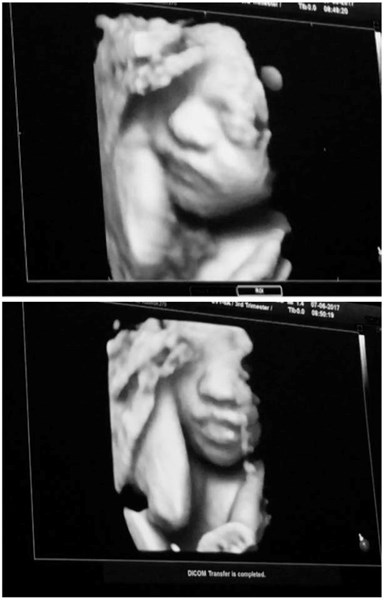

Сървайвърката Янита Янчева показа нероденото си бебе в публичното пространство.

Блондинката е вече в 7-ия месец и с нетърпение очаква първата си рожба в Холандия.

Красавицата е била заедно с мъжа си на 4D ехограф, където са останали изключително доволни и впечатлени от визуализацията на бебето им, научихме от HotArena.net.

„Това беше един от най-емоционалните моменти в живота ми. Нямаме търпение да те гушнем, малко ангелче“, сподели Янита.

Свободното публикуване на 4D снимката обаче възмути повечето суеверни майки. Според поверието до 40-ия ден новороденото не бива да се показва на никого, освен на най-близките.